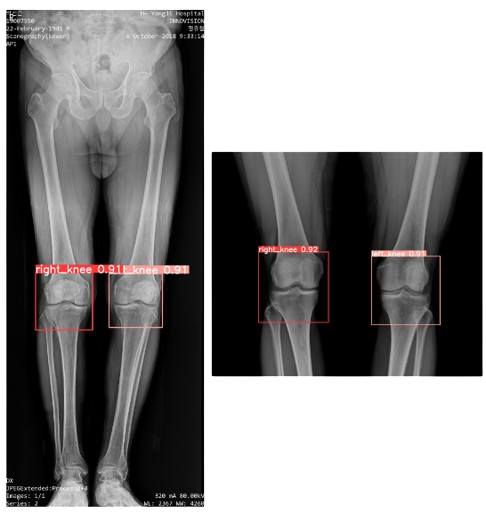

Knee Detection

Trained a versatile YOLOv8 model for knee detection on both full and cropped scanogram images.